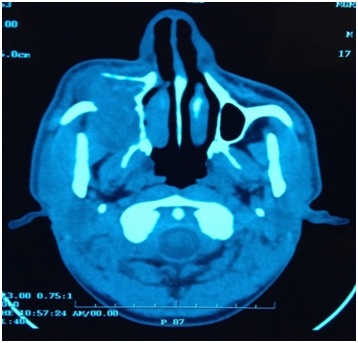

Giant Idiopathic Mucopyocele of Maxillary Sinus Presenting as Asymptomatic Unilateral Facial Swelling: A Case Report

Thakur K, et al.

Dentistry: Advanced Research